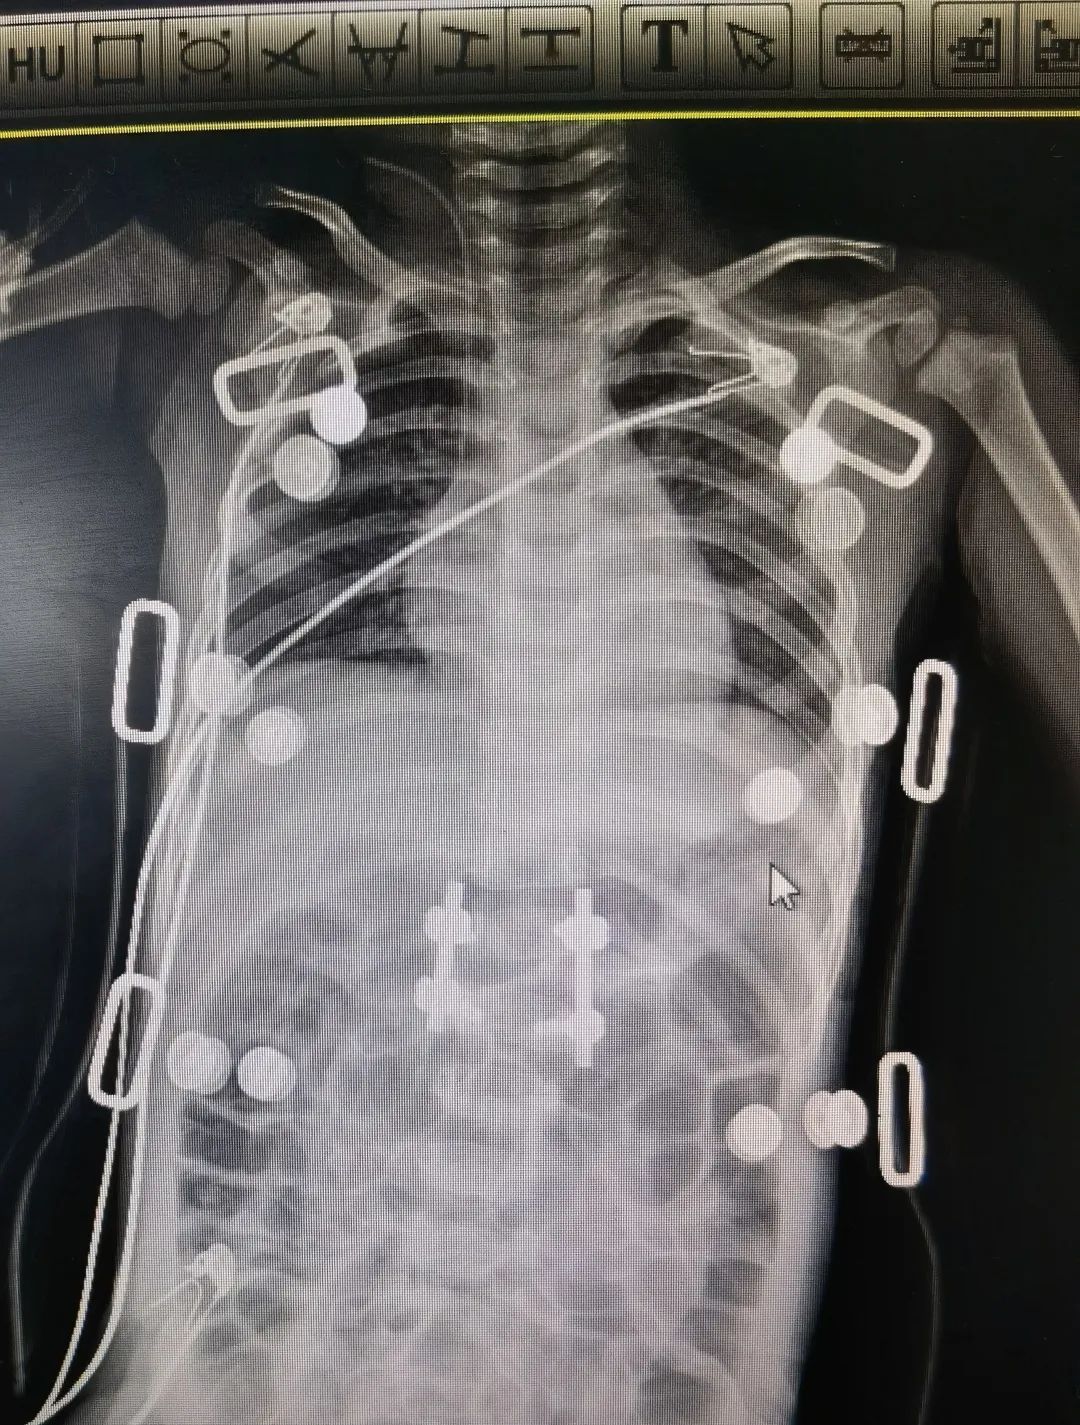

神经肌肉性脊柱侧弯术前术后图

“在这20例的手术里,这个孩子的情况相对特殊,手术难度也比较高。”陈文昊副主任说,“孩子的脊柱侧弯已经达到85°,基本上已经成为一个直角,只能通过手术矫正,如果不手术,这一类型的脊柱侧弯进展会非常快。”

但因为长期生病,玲玲的骨密度非常低,小小年纪已经骨质疏松——她的骨头像70、80岁的老人一样。在弯的最厉害的地方,骨头中根极其纤细,甚至没有,根本打不进钉子。同时神经纤维瘤病的孩子脊髓对矫形的耐受能力较差,为了不影响玲玲的神经和肌力,手术中陈文昊副主任只能降低矫形强度。

克服种种不利因素,手术基本达到了既定的矫正效果,命运坎坷的玲玲在日后也能像其他孩子一样抬头挺胸。